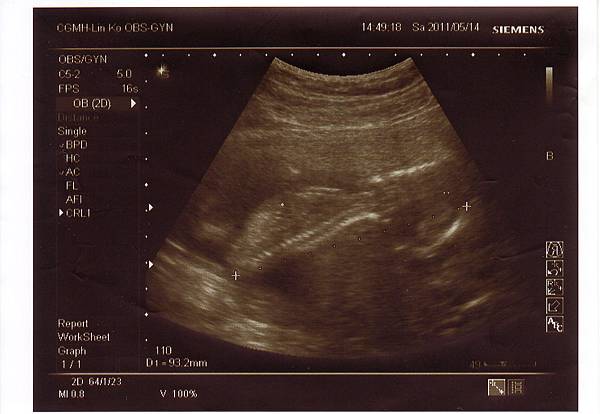

2011.05.14 第二次產檢,醫生雖然不是很確定但說女寶寶的機率比較大,

不論是否為女寶,媽咪只希望你是個健康的寶寶就好了